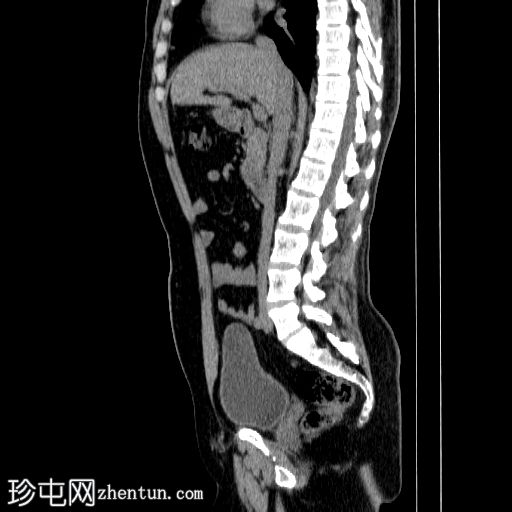

CT

矢状位

平扫

右侧输尿管中段可见一卵圆形不透光结石,最大直径约6 mm,平均CT值约830 HU。该结石伴右侧近端输尿管及肾盂肾盏系统轻度扩张。

左侧输尿管轻度积水,未见明显梗阻性结石。

本病例展示了输尿管结石梗阻的典型CT表现,即上游反压改变。

未见肾周脂肪浸润、穹窿部破裂或尿瘤。